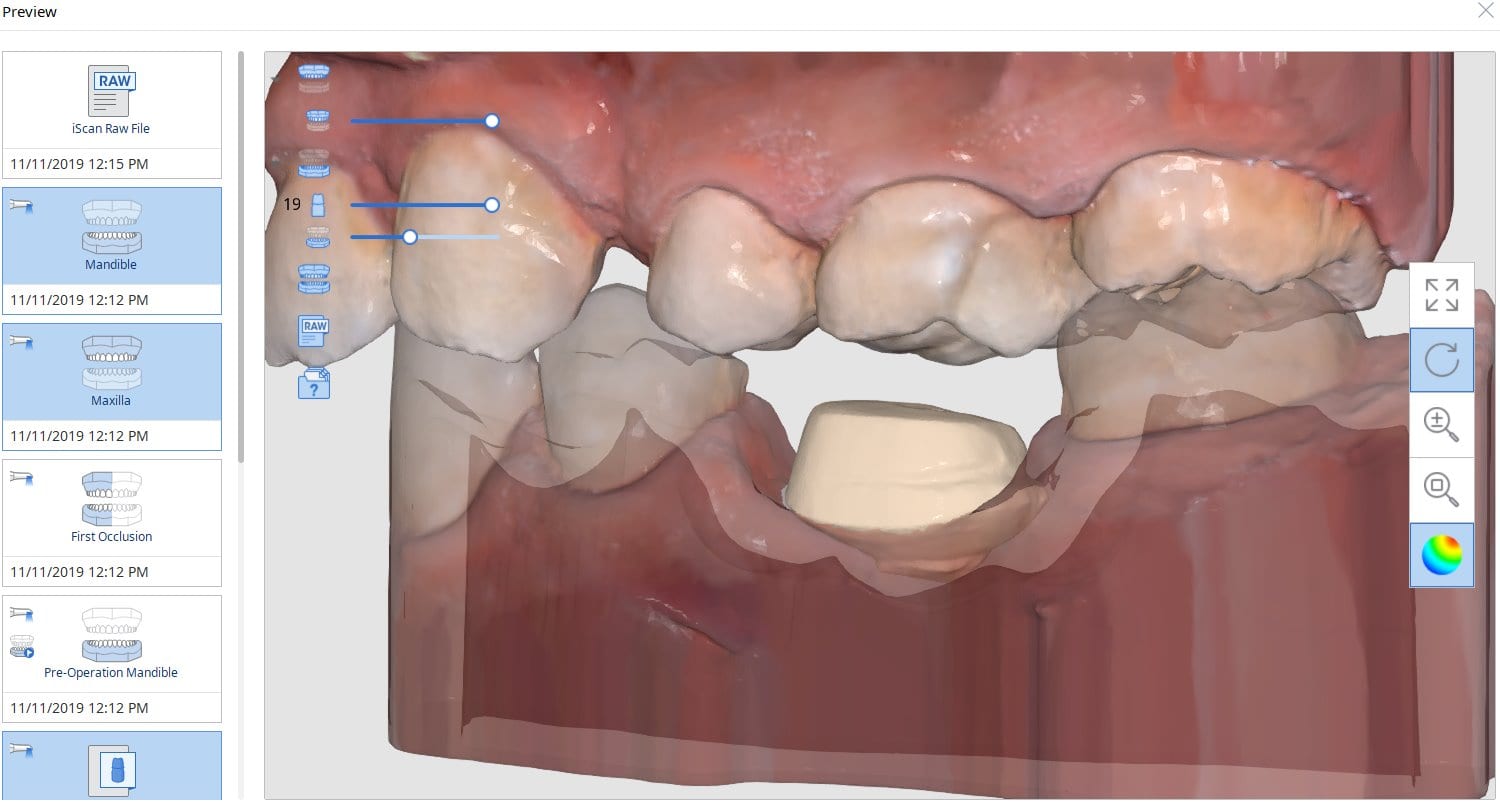

Comparing Milled and Designed Crown Margins

November 19, 2019Have you ever compared the milled product with the designed restoration? We scanned with the medit i500, designed with exocad and milled with coritec. after try-in, we scanned the restoration […]